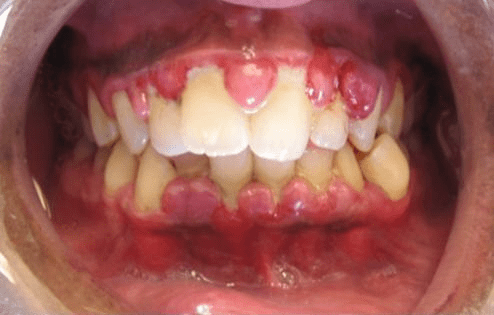

What can gingivitis look like?

Gums are:

- Infected

- Red

- Swollen

- Constant bleeding

What type of disease is this considered?

Gingivitis